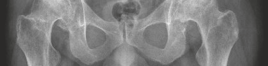

Standard preoperative radiographs included an anteroposterior (AP) pelvis centered over the symphysis pubis with 15 degrees of internal rotation of the lower extremities to profile the femoral necks, alongside true lateral and Dunn lateral views of both hips.

The AP Pelvis radiograph demonstrated severe, bilateral tricompartmental joint space narrowing. The left hip exhibited complete obliteration of the superior and axial joint spaces with bone-on-bone articulation. Subchondral sclerosis was prominent bilaterally, accompanied by marginal osteophyte formation at the femoral head-neck junction and the acetabular rim. Large subchondral cysts (geodes) were visible in the superior weight-bearing dome of the left acetabulum.

The lateral view of the left hip confirmed the loss of sphericity of the femoral head, extensive anterior and posterior osteophytosis, and severe joint space collapse.

The lateral view of the right hip demonstrated similar but slightly less advanced degenerative changes, with marked loss of anterior joint space and reactive subchondral bone formation.